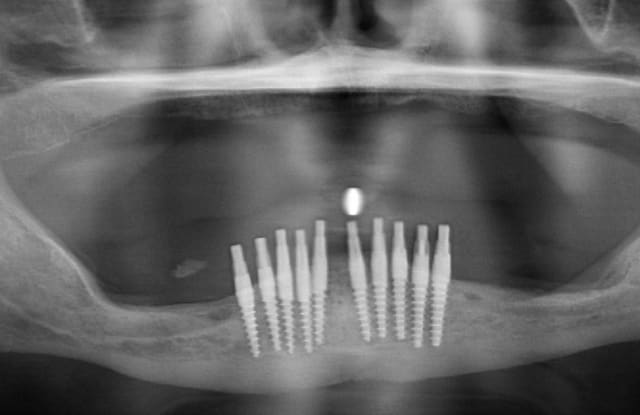

3ème photo: radio d´un patient âgé de 73 ans qui souhaitait avoir des dents fixées.Comme on l´observe il n a plus de place après les foramines mentales.Nous avons donc utilisé juste l´os interforaminal. Nous avons suivi le concept du prof. Nentwig qui consiste à pouvoir ajouter 2 dents dans chaque quadrant dans la mandibule.

Je sais bien que 8 implants auraient suffit cependant 10 ont été posés.Nous voulions remplacer chaque racine avec un implant.

Le patient n a jamais eu de problèmes ( juste avec une hygiène buccale normale, brosse à dents).

Les deux dernières photos montrent le même cas deux ans plus tard.